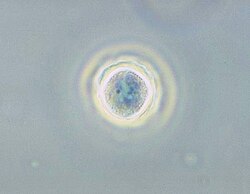

Fazni mikrograf Acanthamoebae polyphagae u obliku mikrobne ciste. | |

Acanthamoeba pripada koljenu Amoebozoa, jednom od najpoznatijih praživotinja u tlu, svježoj vodi i ostalim staništima. Stanice su male, dužine 15 – 35 mikrona, kad se kreću imaju ovalan ili trokutast oblik. Sprijeda, pseudopodije formiraju polukružni režanj, a postranično se vide različite kratke filopodije. Takva organizacija daje akantamebi bodljikav izgled, te je zbog toga i dobila ime akantameba. Ciste su uobičajenog oblika. Večina vrsta su slobodno živuće bakterivore, ali neke su oportunističke bakterije koje mogu izazvati infekcije u ljudi i životinja.